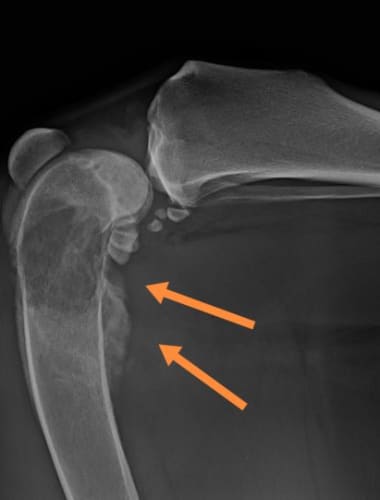

A fokozott nyálzás, véres nyál, rossz szájszag vagy nem gyógyuló bőrelváltozás laphámrákra is utalhat. A diagnózis biopsziával, a kezelés...